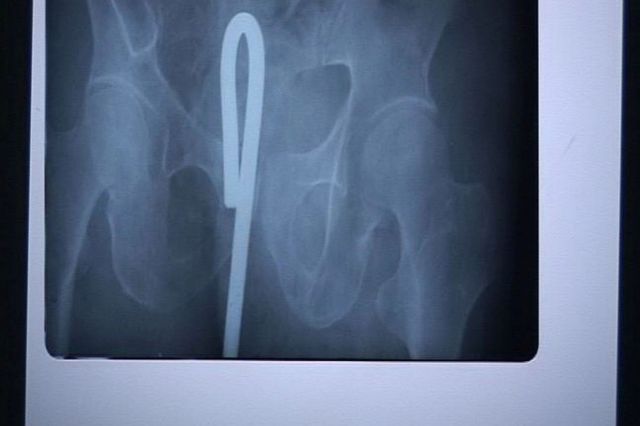

A 13-year-old slipped on an icy school floor in China. Xiao Lin fell forward onto a hook which embedded in his eye. A school handyman sawed the hook off the wall to free the lad, leaving 5cm sticking out of his head. Surgeon Yan Shijun commented: "The hook pierced his skull but was turned to the side by the impact. Any movement would have sent it into his brain and he could have died on the spot." He added: "He has lost his right eye but he's very lucky to be alive at all"